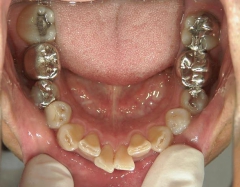

矯正歯科 治療前矯正歯科 治療前

矯正歯科 治療前 右上4番、左右下4番 計3本抜歯し、叢生を改善

矯正_灰色.pngno.22_8175_治療前_下.jpg矯正_灰色.png